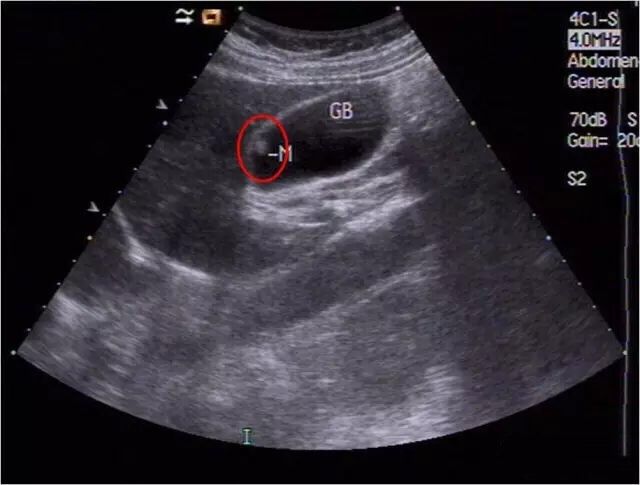

1、消化系统:肝胆胰脾的超声检查。

6、超声引导下的介入诊断及治疗(肝肾囊肿及脓肿穿刺,抽吸,药物灌注,胸腔,纵膈的穿刺活检)